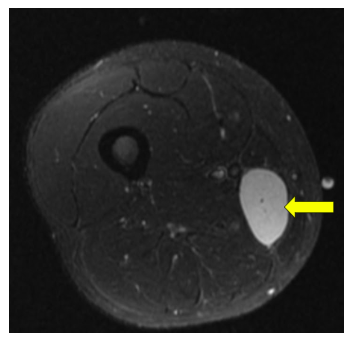

Radiographic imaging is used to help form a diagnosis. These include X-Ray, MRI, CT and Bone Scans

An example of an MRI is shown.